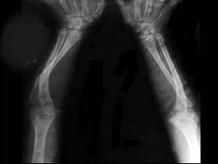

问题 女,2岁,发现蓝色巩膜、听力障碍,四肢畸形等,结合图像,最可能诊断是?(?)

选项 A.维生素D缺乏病 B.维生素C缺乏症 C.软骨发育不全 D.呆小病 E.成骨不全

答案 E